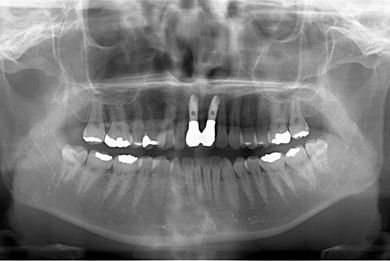

抜歯即日スピードインプラント治療

| 性別/年齢 | 女性 / 32歳 | ||||||||||||||||||||||||||||||||

| 主訴 | 前歯2本の差し歯がぐらついており、インプラントのセカンドオピニオンを希望。 | ||||||||||||||||||||||||||||||||

| 治療方針 | 上顎前歯、抜歯と同時にインプラントを埋入し、治療期間を短縮する。 | ||||||||||||||||||||||||||||||||

| 治療内容 | インプラント2本、メタルボンドセラミッククラウン2本 | ||||||||||||||||||||||||||||||||

| 総治療費 | 909,510円 | ||||||||||||||||||||||||||||||||

| 治療期間 | 1年0ヶ月 |